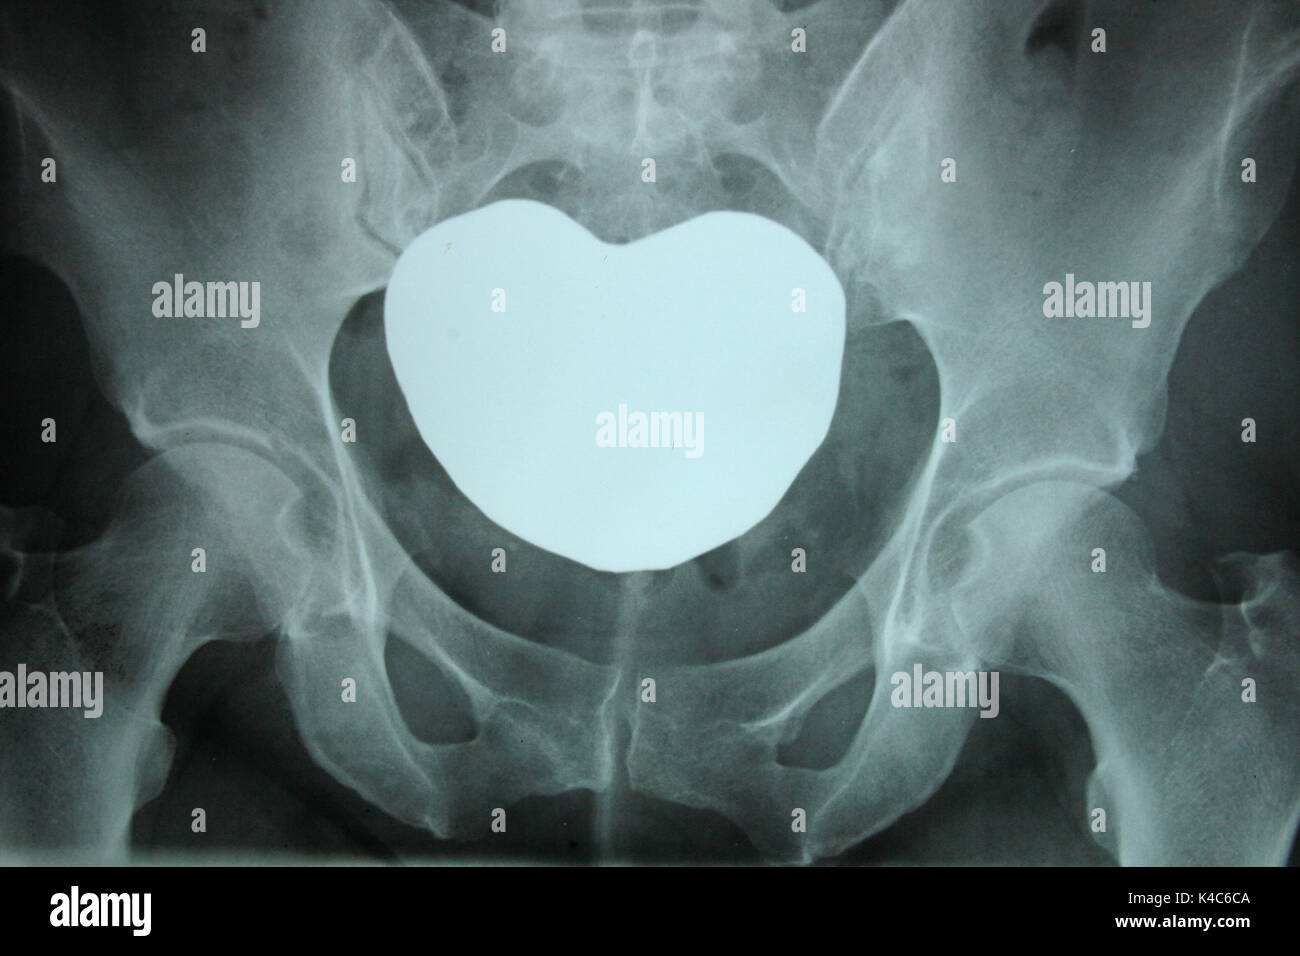

Rayos X Del Cuerpo De Un Hombre - Columna Vertebral, Huesos Pélvicos

es.dreamstime.com

es.dreamstime.com